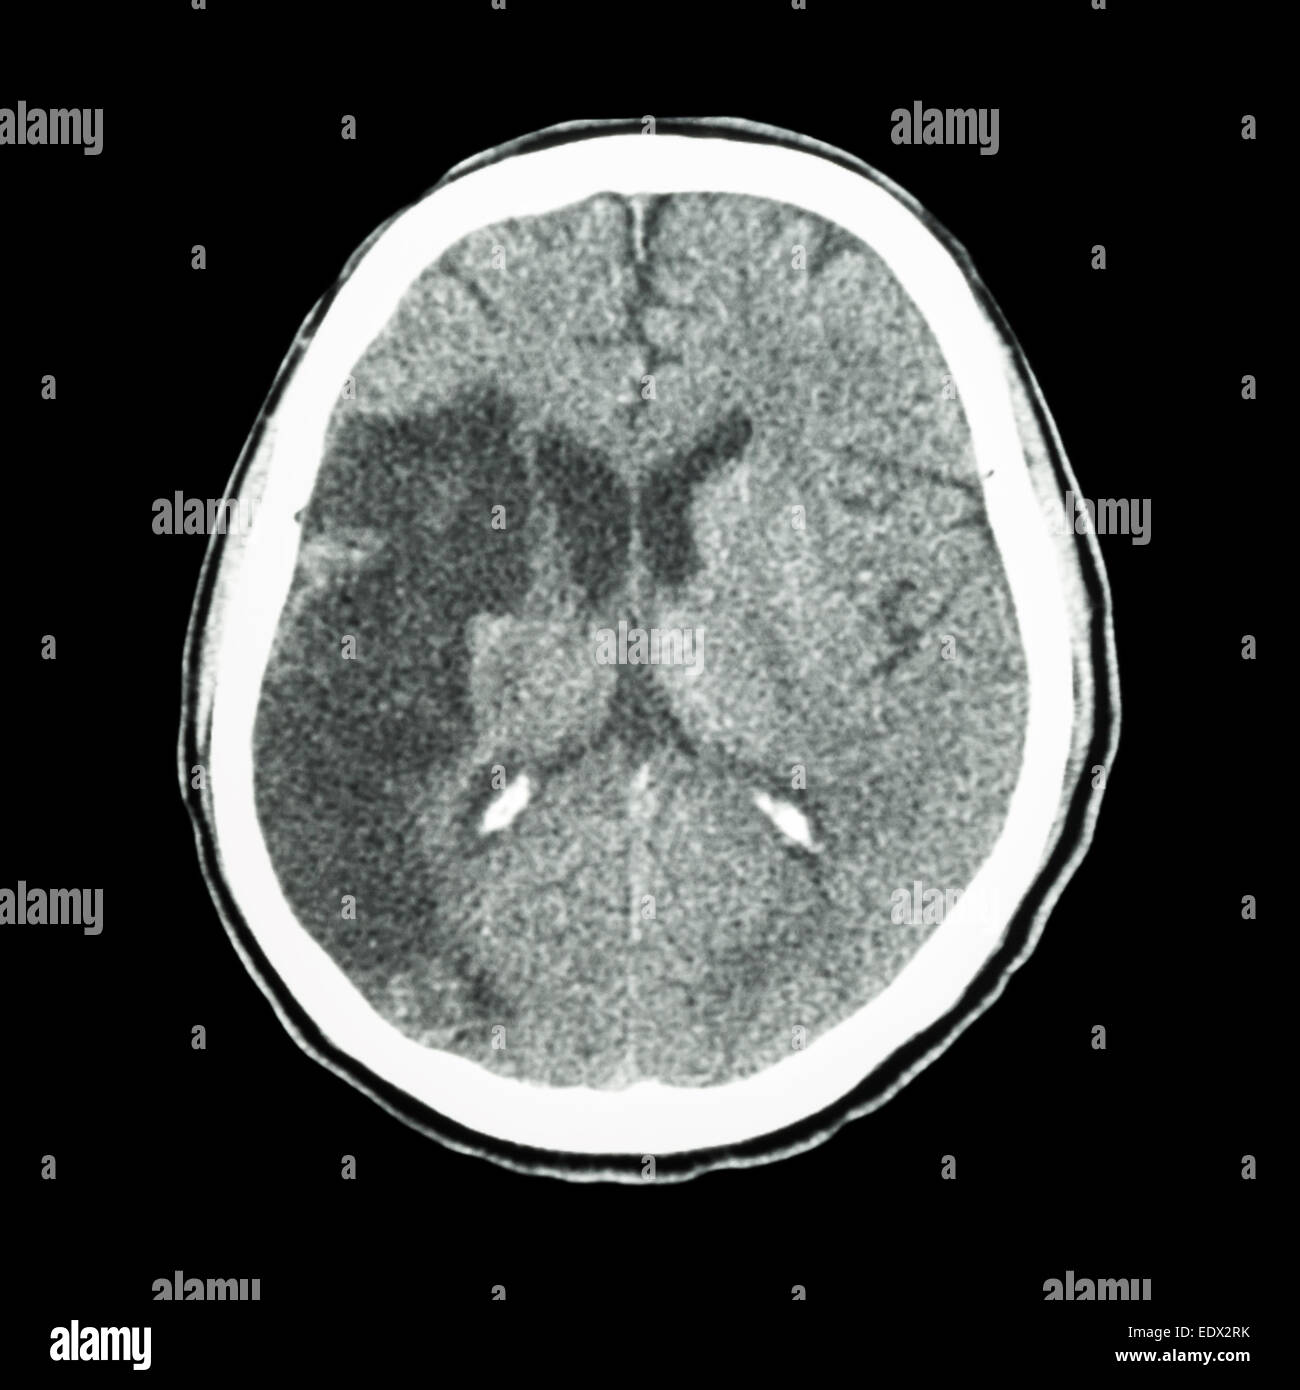

Tc brain : spectacle d'un accident vasculaire cérébral ischémique (hypodensite au-frontal droit lobe pariétal) Banque D'Imageshttps://www.alamyimages.fr/image-license-details/?v=1https://www.alamyimages.fr/photo-image-tc-brain-spectacle-d-un-accident-vasculaire-cerebral-ischemique-hypodensite-au-frontal-droit-lobe-parietal-77404983.html

Tc brain : spectacle d'un accident vasculaire cérébral ischémique (hypodensite au-frontal droit lobe pariétal) Banque D'Imageshttps://www.alamyimages.fr/image-license-details/?v=1https://www.alamyimages.fr/photo-image-tc-brain-spectacle-d-un-accident-vasculaire-cerebral-ischemique-hypodensite-au-frontal-droit-lobe-parietal-77404983.htmlRFEDX2RK–Tc brain : spectacle d'un accident vasculaire cérébral ischémique (hypodensite au-frontal droit lobe pariétal)